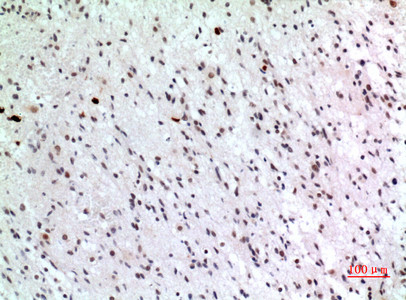

| Short Description | Rabbit polyclonal anti-Cyclin-dependent kinase inhibitor 1C (241-290 aa) for use in WB, IF and ELISA in Human, Mouse and Rat samples. Datasheet included with dilution recommendations, and related reagents. |

| Applications | WB/IF/ELISA |

| Dilution Range | WB 1:500-1:2000IHC-P 1:100-1:300ELISA 1:20000IF 1:50-200 |

| Specificity | p57 Polyclonal Antibody detects endogenous levels of p57 protein. |

| Cellular Localisation | Nucleus |